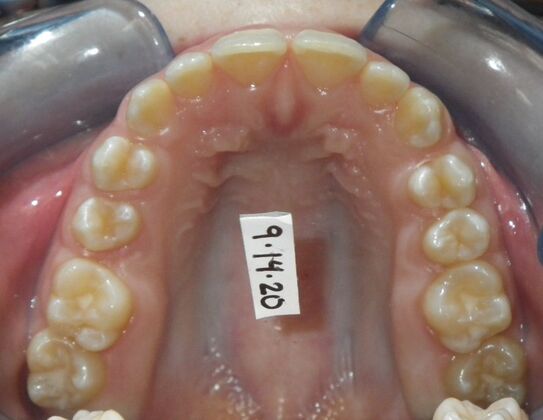

Patient presents desiring all spaces on upper and lower teeth closed. She will need slight expansion of upper arch due to lower molars leaning inward toward tongue. Used nitanium palatal expander with built in rotation of upper molars and lower lip bumper to upright lower first molars. Patient was also informed that her upper lateral incisors would require bonding due to their small size to close all space.